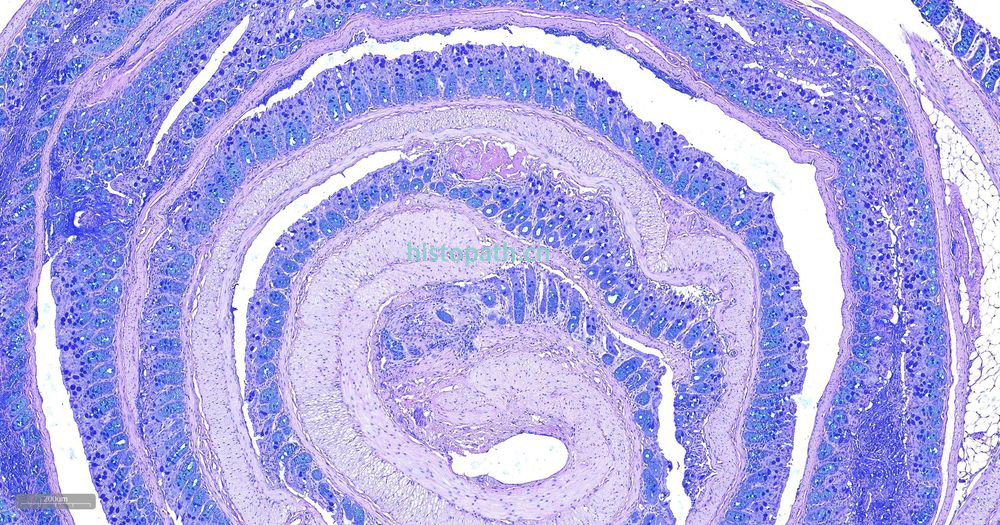

糖原染色是病理学中常规的染色方法之一,该法常用来显示糖原和其他多糖,该染色液不仅能够显示糖原,还能显示中性黏液性物质和某些酸性物质。

阿利新蓝和PAS技术联合使用可鉴别同一组织切片中的中性黏蛋白和酸性黏蛋白。这种技术也常用作广泛检测黏蛋白的手段。阿利新蓝可将唾液黏蛋白、硫黏蛋白和蛋白多糖染成蓝色。PAS技术可将中性黏蛋白染成深红/红紫色,同时将既含中性黏蛋白有含酸性黏蛋白的组织和细胞染成深浅不同的紫色,这是由于阿利新蓝与 Schiff试剂结合并反应。上述染色常可出现在含有中性黏蛋白和唾液黏蛋白的小肠杯状细胞中。

阿利新蓝是类铜钛花青染料,这种阳离子染料与酸性基团结合,也即阿利新蓝与组织内含有的阴离子基团如羧基和硫酸根形成不溶性复合物。分子中带正电荷的盐键与酸性黏蛋白多糖物质中带负电荷的酸性基团结合形成不溶性的复合物而呈蓝色,再与PAS进行复合染色,就能显示三种不同黏液物质成分。